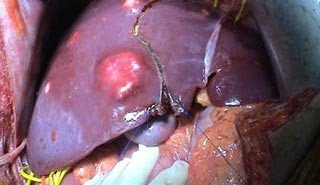

Şəkil 2. Qaraciyər absesində müalicə və proqnoz

Abses diaqnozunu dəqiqləşdirmək üçün klinik əlmətlərlə yanaşı görüntüləmə və laborator müayinələr aparılmalıdır. Yerli və ümumi sepsis əlamətləri ilə yanaşı USM və ya tomoqrafiyada qaraciyərdə abses boşluğun görünməsi diaqnozu dəqiqləşdirir. Absesdə qaztörədən bakteriyalar olduqda və ya bağırsağa açılarsa içərisində qaz görünür (25%).

Diaqnostik əlamətləri:

• Ağrı, hepatomeqaliya, hərarət, septik əlamətləri

• Laborator septik əlamətlər

• Görüntüləmədə destruktiv ocaq